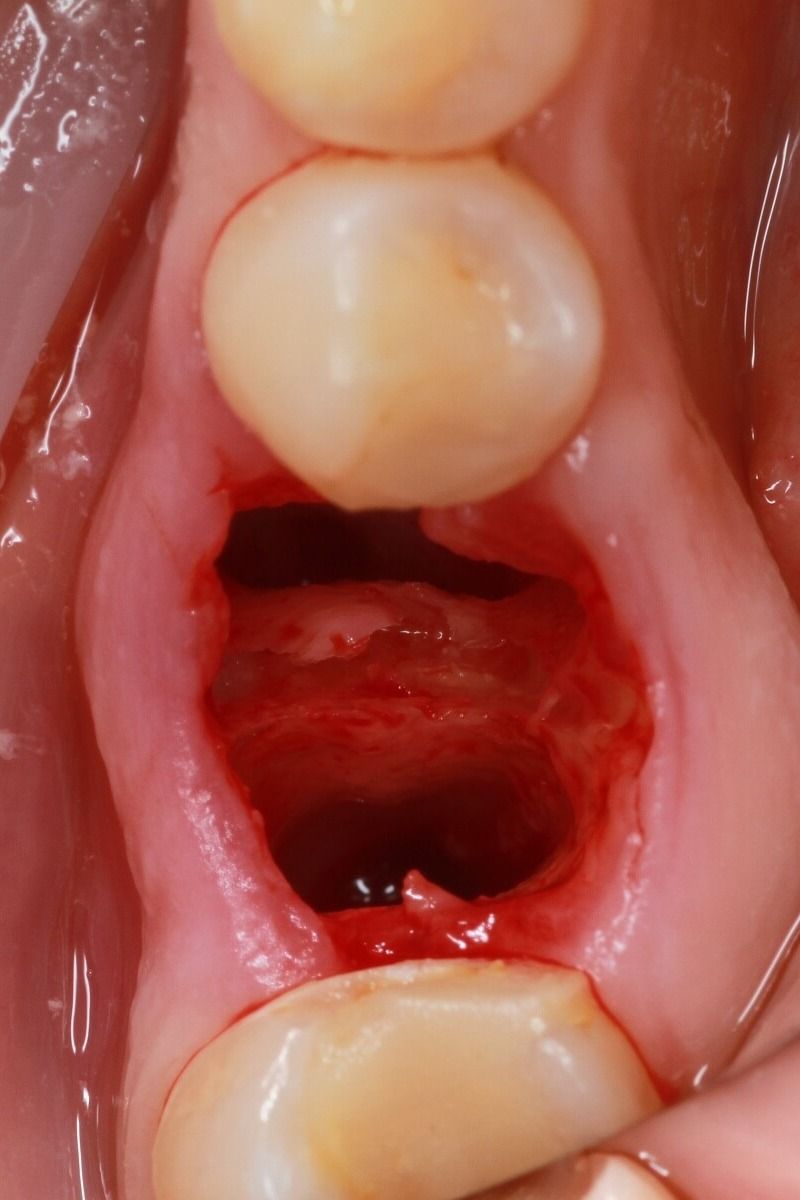

Implantation immediately after careful tooth extraction is the best way to save tissue.

In our clinic, implantation is often accompanied by an additional increase in bone volume and an increase in the height of soft tissues. This is done to preserve aesthetics and preserve the implant. So that the implantation site is not visible, we create a single level of the gum, the same as that of the adjacent teeth. And the same is done to prolong the life of the implant, because it is the gum, which is tightly attached to the crown, that is the barrier that protects the implant from bacteria.